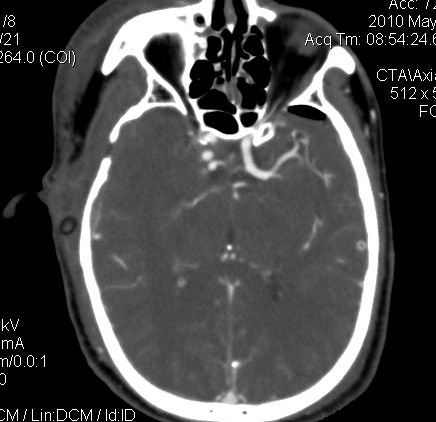

男.60岁,渐进性意识不清,ct检查双侧额颞顶部硬膜下血肿,开颅术后行脑血管cta,大脑中动脉起始部见一瘤状血管扩张。请各位老师留下宝贵意见

太常见了,报动脉瘤就可以

符合动脉瘤表现。

符合动脉瘤表现。

动脉瘤。

颅内动脉瘤。

后重建做得不是很好看,要将维蒂斯环充分显示,最好在增加一个mip。这样不好定位。

小动脉瘤

典型

符合动脉瘤的表现

动脉瘤

符合动脉瘤表现。

小动脉瘤

典型